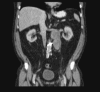

Retroperitoneal lymph node dissection (RPLND) is a prognostic, palliative, and potentially therapeutic procedure for patients with malignant phenotype Leydig cell tumours of the testis. We reviewed the records of patients diagnosed with malignant phenotype Leydig cell tumours of the testis treated by RPLND. Modified template dissection was performed in all cases with extra-template excision of tumour mass in Stage II disease. Routine clinico-radiological follow-up was performed. Six open RPLNDs (1 re-do procedure) were performed on 5 patients diagnosed with Stage I (n = 3) and Stage II (n = 2) malignant phenotype Leydig cell tumour of the testis. Median age = 63 years (range = 55-72). Median peri-operative blood loss = 1500 ml (range = 500-1500 ml). Median operating time = 6 h (range = 4.5-6.5). Two patients with Stage II disease developed post-operative complications of acute kidney injury (n = 1) and pneumonia (n = 1). Median length of stay was 8 days (range = 6-11). RPLND specimens from patients with Stage I were tumour-free, whilst patients with Stage II disease had evidence of metastatic tumour. At latest follow-up (median = 13 months, range = 7-22), no patient with Stage I disease had radiological evidence of recurrence, however the two patients with Stage II disease had died due to tumour recurrence at 13 months and 36 months. RPLND for malignant phenotype Leydig cell testicular tumours appears to be well tolerated. Despite surgery, overall outcomes for Stage II appear to be poor due to the disease phenotype. Larger prospective multi-centre studies are required to determine the definitive criteria for surgery in Stage I disease.